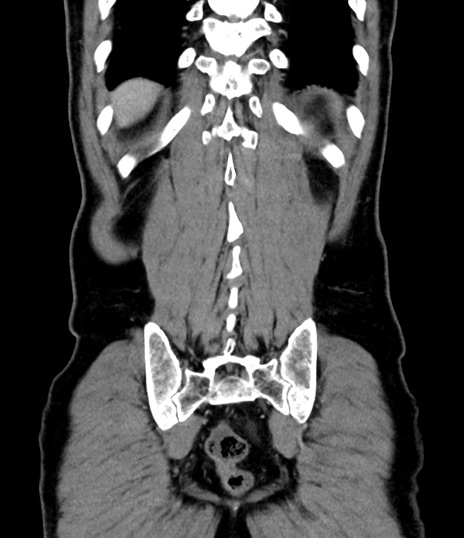

症例8(冠状断像)

【症例】 60歳代男性

【主訴】 黒色吐物

【現病歴】 4日前から嘔気自覚、2日前の朝食後にも嘔気あり、自分で手で嘔吐反射起こし嘔吐したところ血が混ざっていたため受診。

【既往歴】 5年前汎発性腹膜炎を伴う急性虫垂炎で手術、高血圧、前立腺肥大症、高脂血症

【身体所見】 腹部正中に手術癩痕あり 腹部平坦・軟圧痛なし膨満感あり

【データ】WBC 8400、CRP 4.54